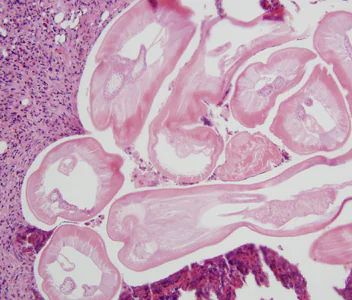

Dirofilaria immitis is usually diagnosed by the finding of the distinctive coin lesions on chest X-rays. The species that produce subcutaneous nodules are diagnosed by the finding of adult worms in biopsy specimens of these nodules. The morphologic features of the cuticle, musculature, and lateral chords are important criteria for identifying Dirofilaria. Worms removed from the eye are usually diagnosed by external features of the cuticle; worms may also be processed by routine histologic methods to study the internal structures. There are currently no serologic or molecular methods available in the United States for diagnosis of human dirofilariasis.